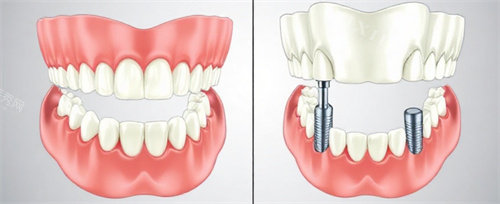

在牙齿种植方面,嘉洁口腔根据患者口腔情况制定方案。种植过程分为几个步骤,从检查到完成需要一定周期。机构使用的种植材料符合相关标准,能够满足不同患者的需求。对于牙齿缺失的患者来说,种植牙是一种常见的修复方式。